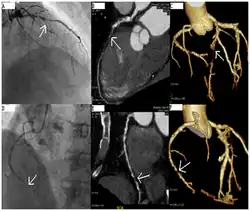

CT angiography can act as a less invasive alternative to Catheter angiography. Instead of a catheter being inserted into a vein or artery, CT angiography involves only the injection of a CT-visible dye into the arm or hand via an IV line. CT angiography lowers the risk of arterial perforation and catheter site infection. It provides 3D images that can be studied on computer, and also allows measurement of heart ventricle size. Infarct area and arterial calcium can also be observed (however those require a somewhat higher radiation exposure). That said, one advantage retained by Catheter angiography is the ability of the physician to perform procedure such as balloon angioplasty or insertion of a stent to improve blood flow to the artery.[8]